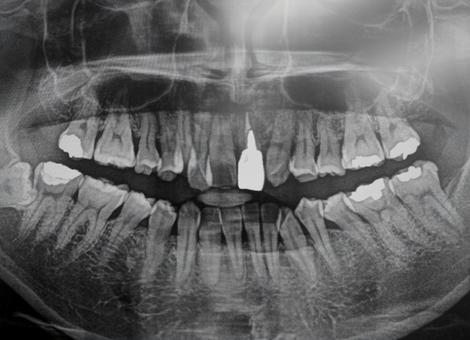

レントゲン検査は、歯や歯茎、顎の骨の状態を確認するための検査です。肉眼では見えない部分の骨の減り具合や歯の根の状態などを詳しく調べることができます。